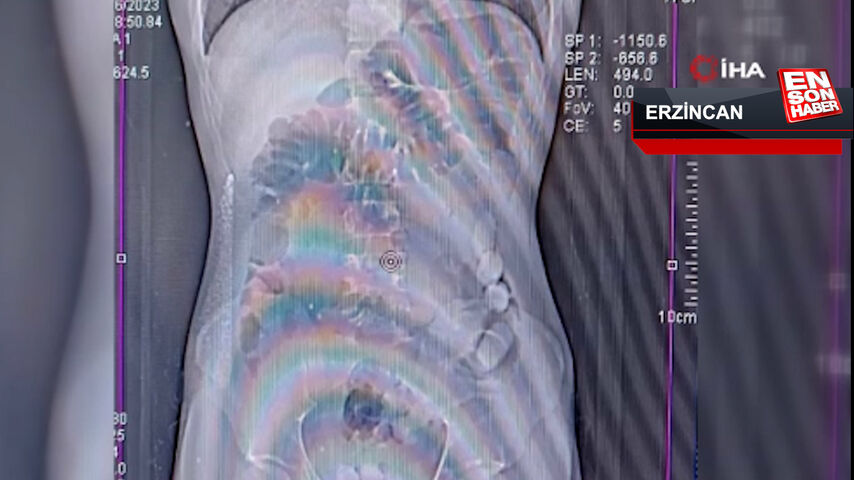

Erzincan polisinin uyuşturucu madde kuryeliği yapan şahıslara yönelik düzenlediği operasyonda, uyuşturucuyu midesine gizleyen İran uyruklu 2 kişi tutuklandı. 1,748 gr Afyon sakızı ele geçirildi.